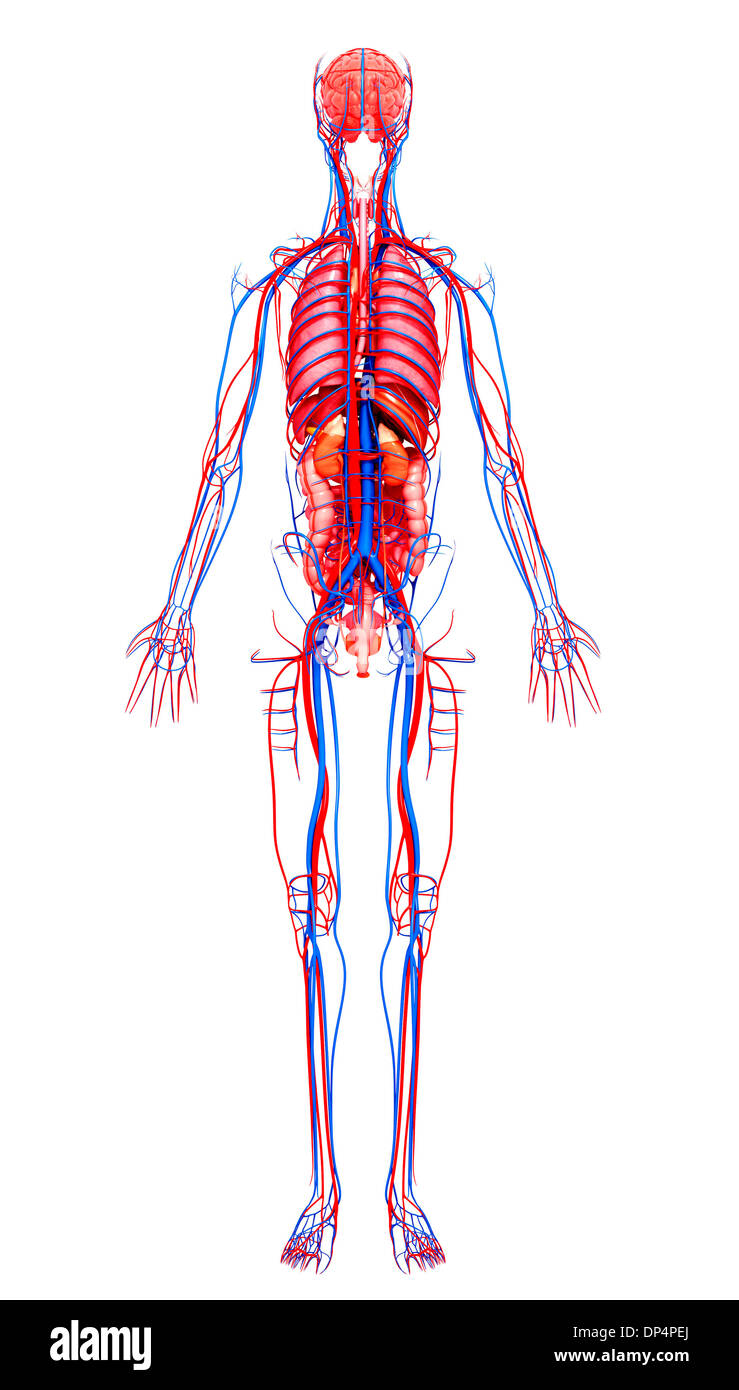

Human Anatomy, artwork Banque D'Imageshttps://www.alamyimages.fr/image-license-details/?v=1https://www.alamyimages.fr/human-anatomy-artwork-image65259002.html

Human Anatomy, artwork Banque D'Imageshttps://www.alamyimages.fr/image-license-details/?v=1https://www.alamyimages.fr/human-anatomy-artwork-image65259002.htmlRFDP4PEJ–Human Anatomy, artwork